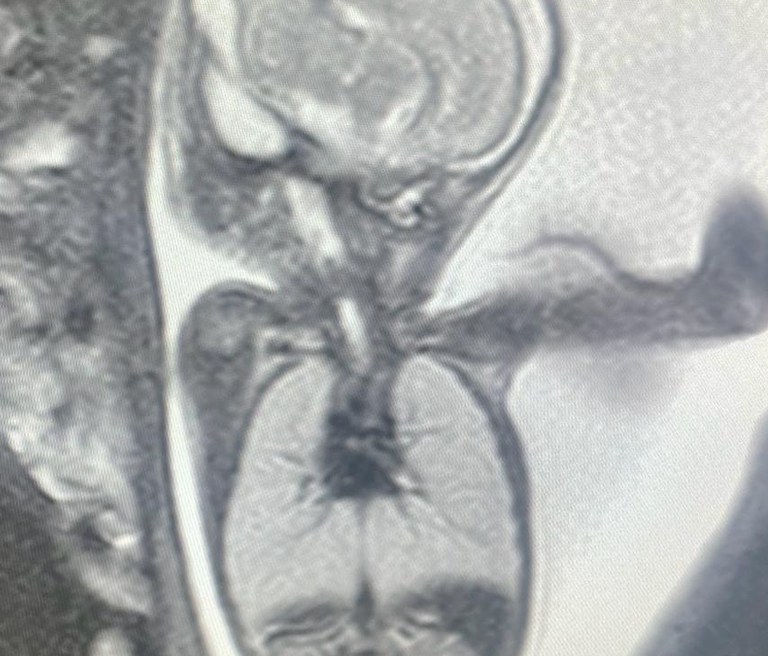

Hypospadias

The urethra's entrance is not near the tip of the penis, but rather on the bottom in a condition known